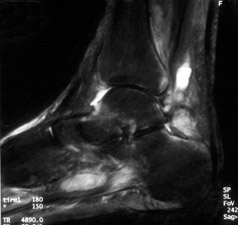

55-year-old man with

long standing diabetes. He had ulcer formation of the posterior ankle and hindfoot, with

markedly swollen ankle. Sagittal STIR image demonstrates ankle effusion and reactive bone

marrow edema at the anterior and posterior aspects of the distal tibia, anterior and

posterior talus, and superior calcaneus. These represent the "bare areas" of the

ankle joint where protective articular cartilage ends. These areas are the first to show

marrow signal change in inflammatory and/or infectious arthritis. (Click on the

image to see a larger version)